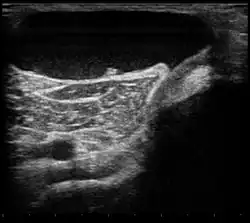

| Ultrasound image of Baker's cyst | |

| Diagnostic method | Confirmed by ultrasound or MRI[3] |

Risk factors include other knee problems such as osteoarthritis, meniscal tears, or rheumatoid arthritis.[1][3][4] The underlying mechanism involves the flow of synovial fluid from the knee joint to the gastrocnemio-semimembranosus bursa, resulting in its expansion.[1] The diagnosis may be confirmed with ultrasound or magnetic resonance imaging (MRI).[3]

Diagnosis is by examination. A Baker's cyst is easier to see from behind with the patient standing with knees fully extended. It is most easily palpated (felt) with the knee partially flexed. Diagnosis is confirmed by ultrasonography, although if needed and there is no suspicion of a popliteal artery aneurysm then aspiration of synovial fluid from the cyst may be undertaken with care. An MRI image can reveal presence of a Baker's cyst.